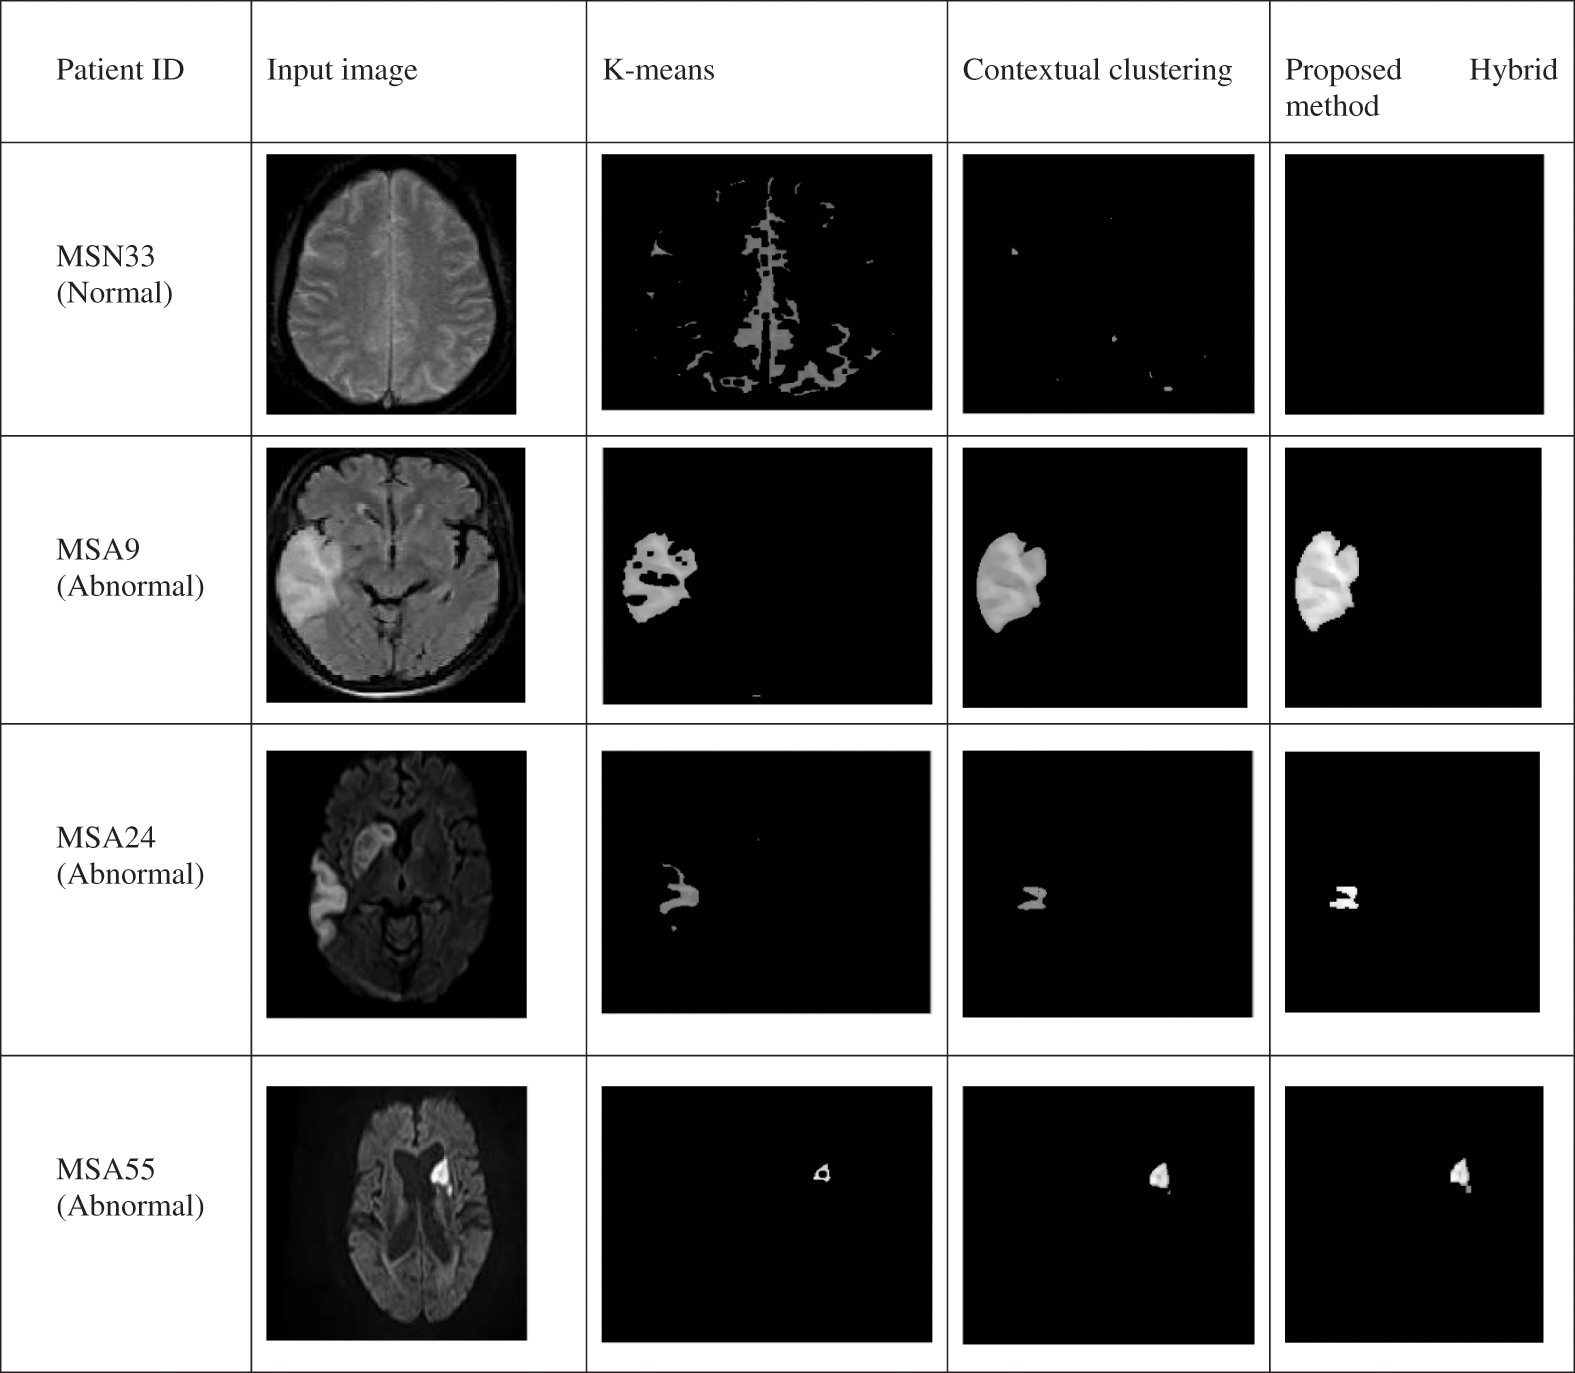

Figure 3: a. Input image, b. Resized image, c. Image after denoising, d. Skull stripped image, e. Morphological opening image, f. Segmentation with multiple iteration, g. Region of interest result of PSO, h. Affected region K-means Clustering, Contextual clustering and Proposed Hybrid method have been applied across input MRI normal and abnormal images and result of patients MSN33, MSA9, MSA24, MSA55 is shown in Fig. 4 and nearly 12 parameters are determined and it is shown in Tabs. 1 and 2. From the Fig. 4 it is observed that proposed hybrid algorithm gives better results as compared to K-means and Contextual clustering algorithm

Figure 4: Comparison of different segmentation techniques